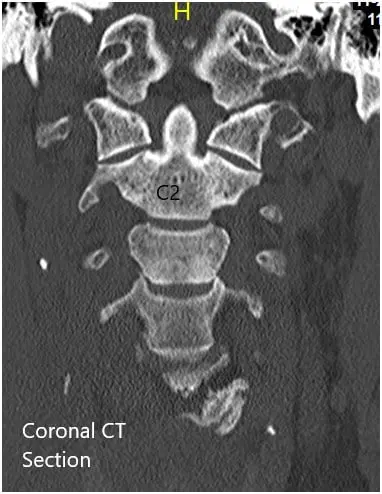

CT of the cervical spine demonstrated multilevel posterior disc bulges with bilateral neural foraminal stenosis of the mid to lower cervical spine. Sclerotic hypertrophic degenerative changes were associated with the mid to lower cervical facets.

Preoperative Coronal and Axial CT sections

Preoperative Coronal and Axial CT sections 2

Preoperative Coronal and Axial CT sections.